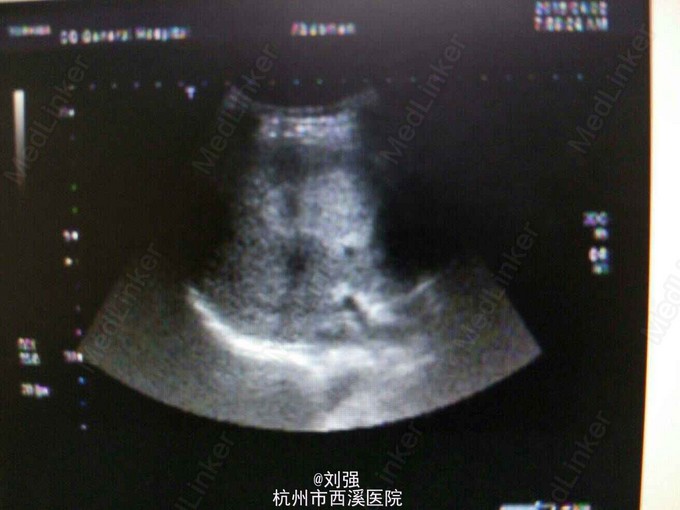

查体:生命体征平稳,心肺无特殊。腹部外形正常,腹式呼吸存在,无压痛以及反跳痛,肝区叩击痛阳性。辅助检查:实验室检查提示白蛋白下35.97g/L。腹部彩超提示:肝S5一大小为4.3cmX3.5cm实质性病灶,考虑血管瘤。腹部MRI检查提示S5段血管瘤。